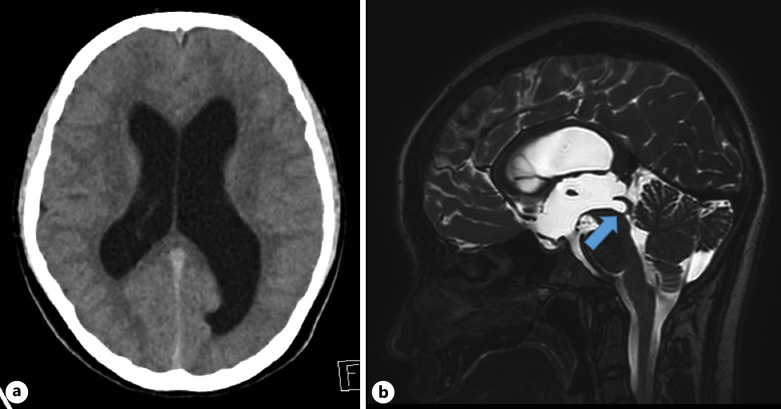

Case presentation: A 16-year-old girl with no relevant medical history presented with a 1-week history of binocular diplopia without any loss of visual acuity in either eye. At the time of her visit, she had no symptoms of headache or vomiting. Examination of eye movements revealed bilateral abduction deficits and fundoscopic examination showed bilateral optic disc swelling. Non-contrast computed tomography of the head indicated hydrocephalus. Contrast-enhanced magnetic resonance imaging of the head revealed significant dilatation of the lateral and third ventricles but not in the fourth ventricle. Sagittal T2-weighted imaging with constructive interference in the steady state showed membranous occlusion of the cerebral aqueduct. The patient underwent an endoscopic third ventriculostomy. Binocular diplopia improved during the early postoperative period.